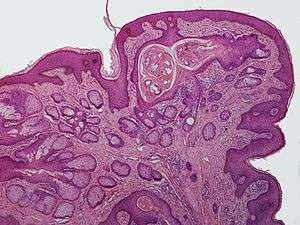

Nevus sebaceus or sebaceous nevus (the first term is its Latin name, the second term is its name in English; also known as an "Organoid nevus"[1]:661 and "Nevus sebaceus of Jadassohn"[2]:773) is a congenital, hairless plaque that typically occurs on the face or scalp.[3] Such nevi are present at birth, or early childhood, affecting males and females of all races equally.[4] The condition is named for an overgrowth of sebaceous glands in the area of the nevus.

Skin growths such as benign tumors and basal cell carcinoma can arise in sebaceous nevi, usually in adulthood. Rarely, sebaceous nevi can give rise to sebaceous carcinoma.[5] However, the rate of such malignancies is now known to be less than had been estimated. For this reason, excision is no longer automatically recommended.[6]